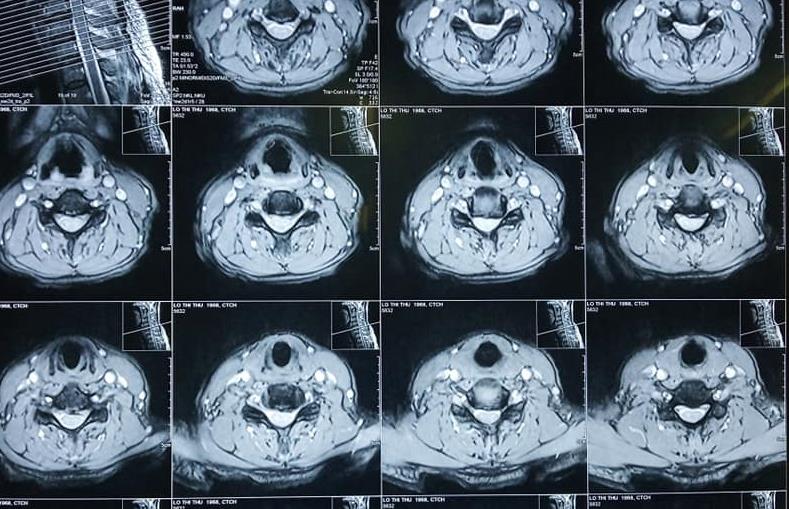

Niềm vui của bệnh nhân được phục hồi sau thoái hóa đốt sống cổ

Bệnh nhân Lô Thị Thư ở Nghĩa Đàn, Nghệ An được chuyển tuyến đến Bệnh viện Chấn thương Chỉnh hình Nghệ An trong tình trạng sức khỏe yếu, đau đầu nhiều, sưng nề vùng mặt, đau hạn chế vận động cột sống cổ, tê bì hai tay, không ngồi dậy được.